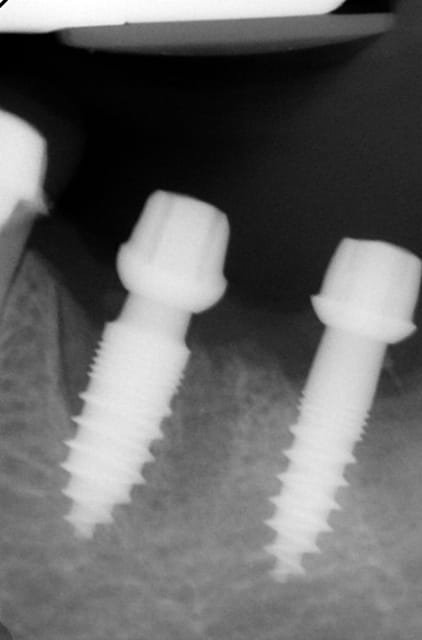

Maintenant concernant la demande de scans : je poste ce cas, une patiente vient me voir avec son scan car elle a consulté d'autres "spécialistes" et on lui refuse la pose d'implant secteur 4 où alors avec greffe préalable..Ca se discute..pas de temps à perdre je sais faire autrement..

Avec la chir trans gingivale technique MIMI ( Oui..un post sur la technique bientôt ..) j'ai pu placer deux 3,5/8mm..aurai je eu le meme résultat avec un lambeau..j'en doute..Les couronnes sont en titane. Recul clinique 2 ans ras. Simple efficace rapide moins onéreux satisfaisant pour le praticien et la patiente..